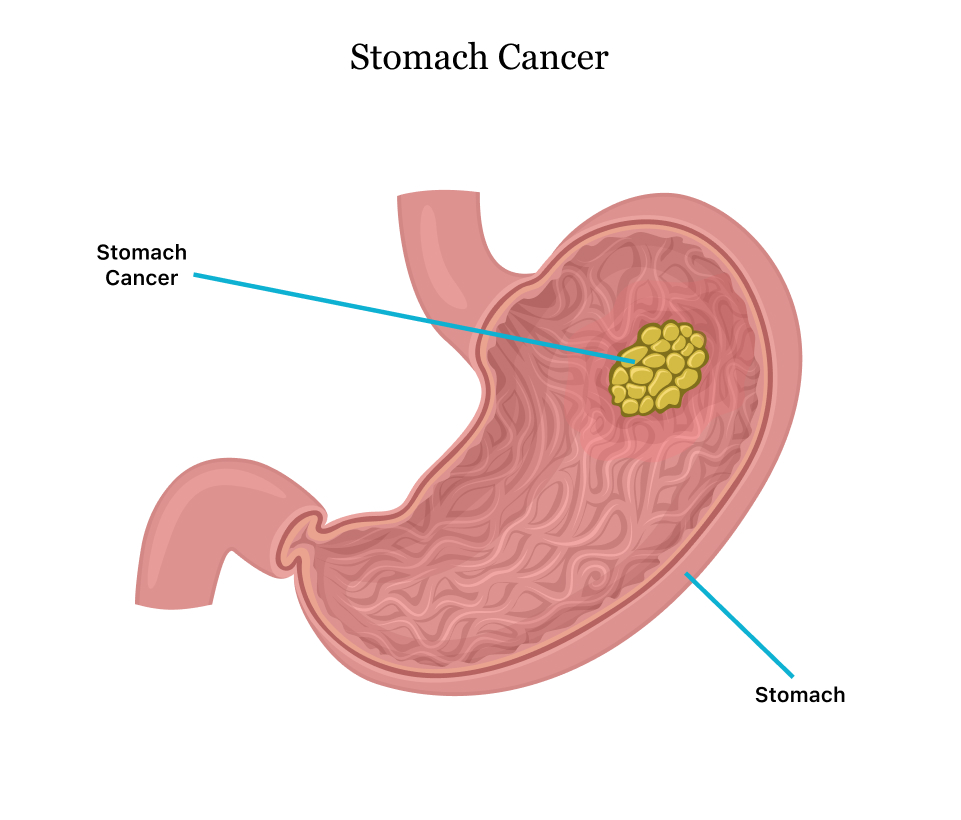

Vector Isolated Illustration of Stomach Cancer Stock Vector …

Vector Isolated Illustration of Stomach Cancer Stock Vector …

Vector Isolated Illustration of Stomach Cancer Stock Vector …